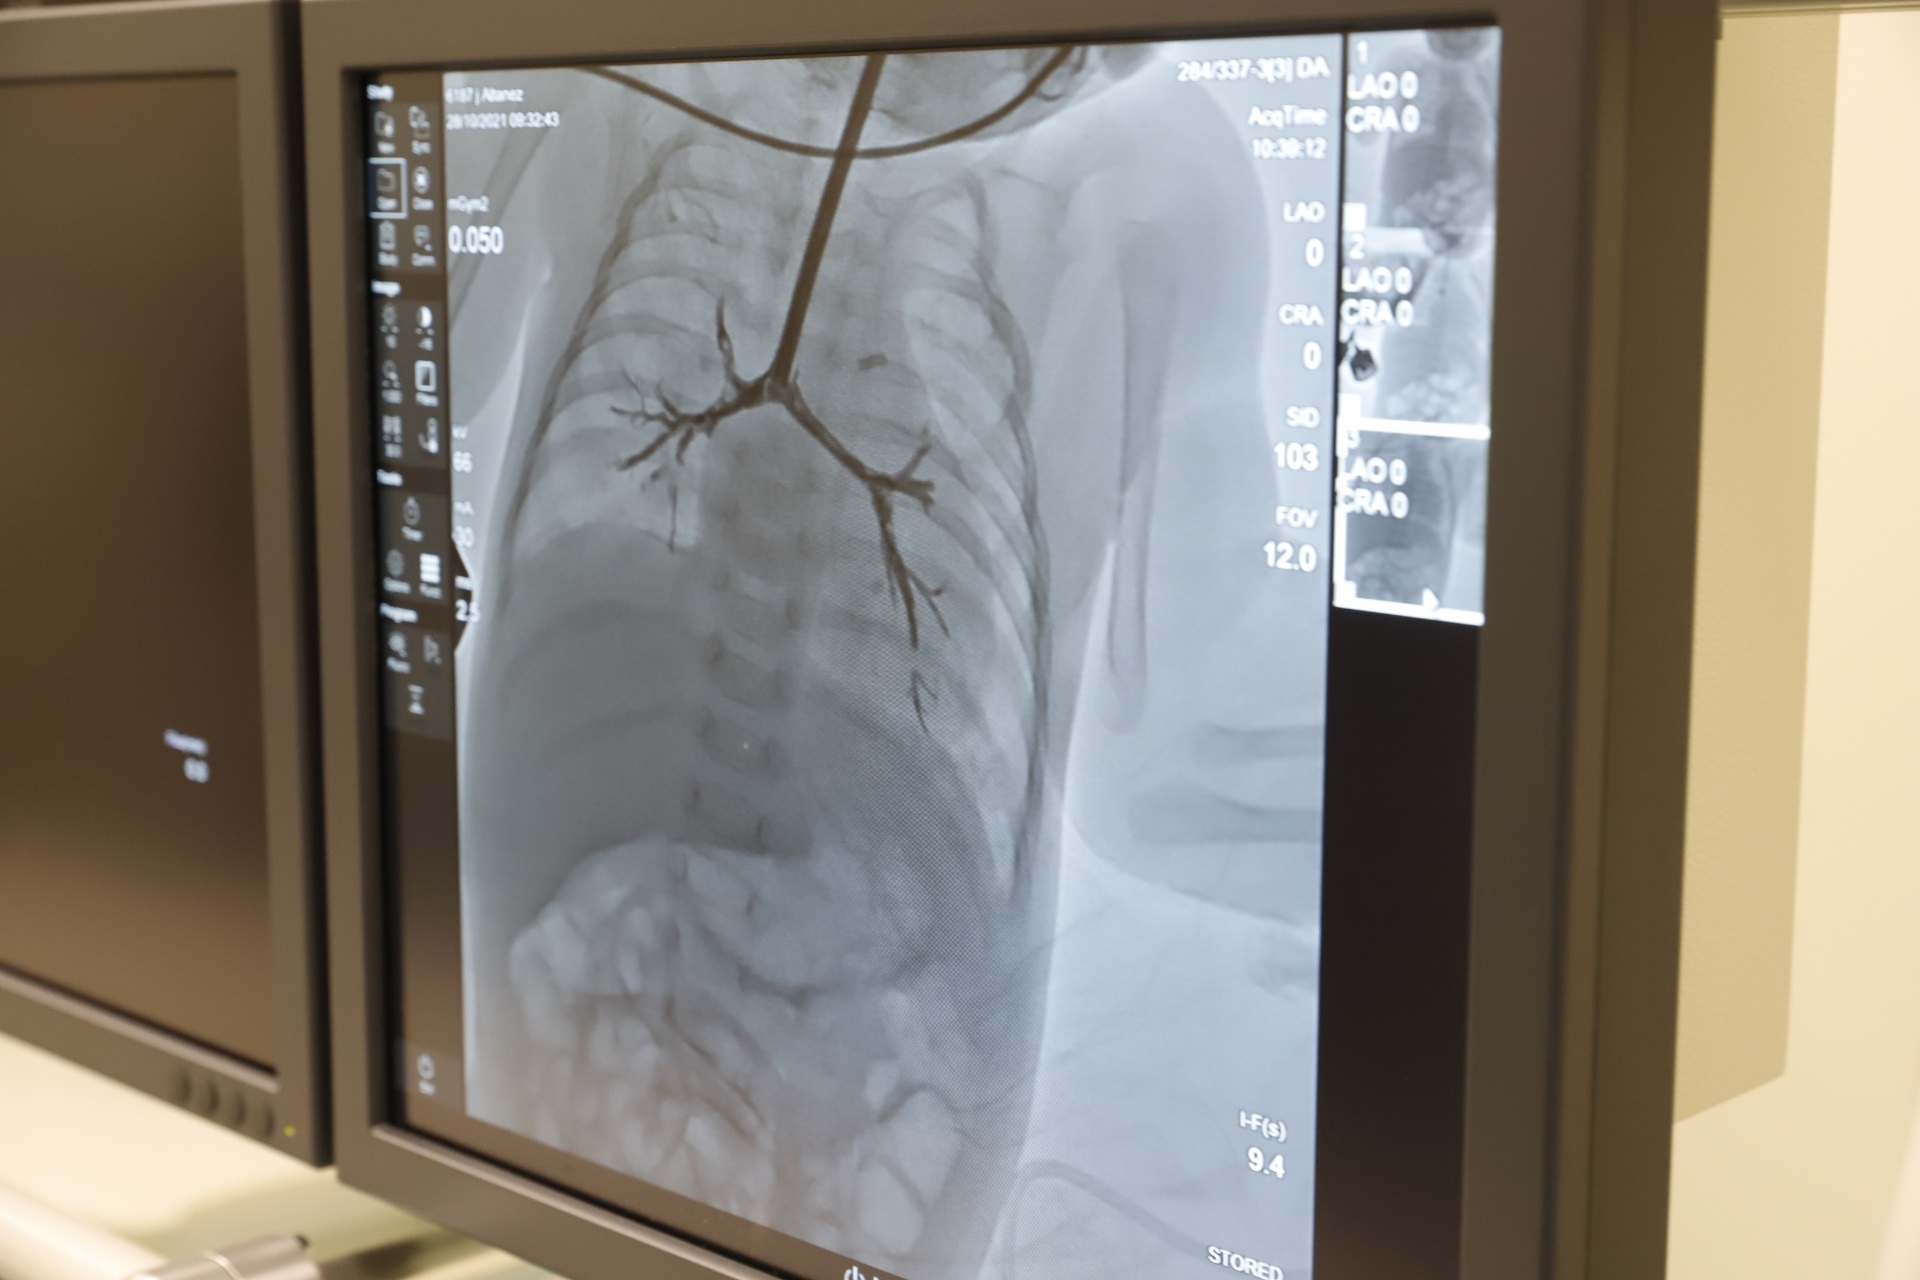

Врачи провели достаточно редкую процедуру – баллонную дилатацию трахеи. При этом не было полной уверенности в том, что она поможет решить проблему. Однако после консультации со специалистами из Института сердца МОЗ днепровские врачи все же решились на процедуру. Когда девочке проводили операцию неделю назад, ее вес был всего 2,8 килограмма.

На втором этапе ей провели оперативное вмешательство, во время которого успешно устранили порок сердца. Для этого в Днепр из Киева прибыла бригада медиков. Отправить младенца в другой город не могли, так как она могла просто не пережить длительной поездки.

Основной этап операции длился 2,5 часа, еще около полутора часа ее готовили к вмешательству. Сердце крохи остановили на 38 минут. Все это время оно не сокращалось, а легкие не дышали. Вместо сердца у девочки работал аппарат искусственного кровообращения.